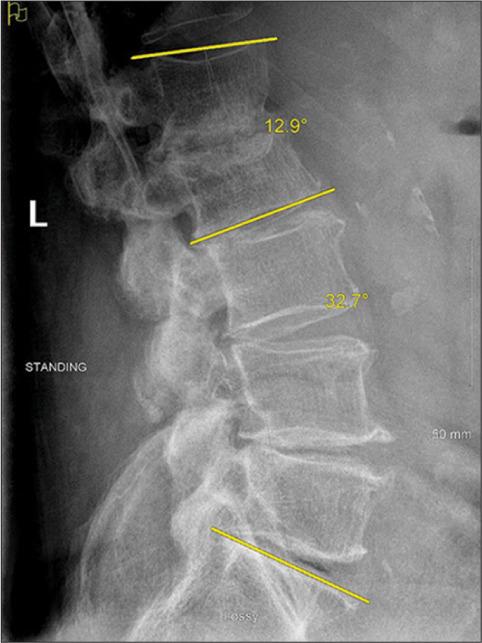

A 77-year-old male presented with L1-2 TB osteomyelitis secondary to intravesical BCG application. A 36.1° focal nonfixed kyphotic deformity was evident on standing X-rays that reduced in the supine position. He underwent posterior percutaneous screw fixation with rods extending from the T12 to L3 levels, with resolution of his mechanical pain. Nine months later, the CT demonstrated reconstitution of the vertebral bodies (i.e., volume increase of 6.99 cm (21%) and 7.49 cm (27%) at L1 and L2, respectively). Standing X-rays after hardware removal demonstrated 32.7° of lumbar lordosis and a reduction of focal kyphosis to 12.9°.

一名77岁男性因膀胱内应用卡介苗继发L1-2节段结核性骨髓炎。站立位X线片显示明显的36.1°局灶性非固定性后凸畸形,仰卧位时畸形减轻。他接受了从T12至L3节段的后路经皮螺钉固定及棒植入,机械性疼痛得到缓解。9个月后,CT显示椎体重建(即L1和L2椎体体积分别增加6.99 cm(21%)和7.49 cm(27%))。取出内固定后的站立位X线片显示腰椎前凸为32.7°,局灶性后凸畸形减轻至12.9°。